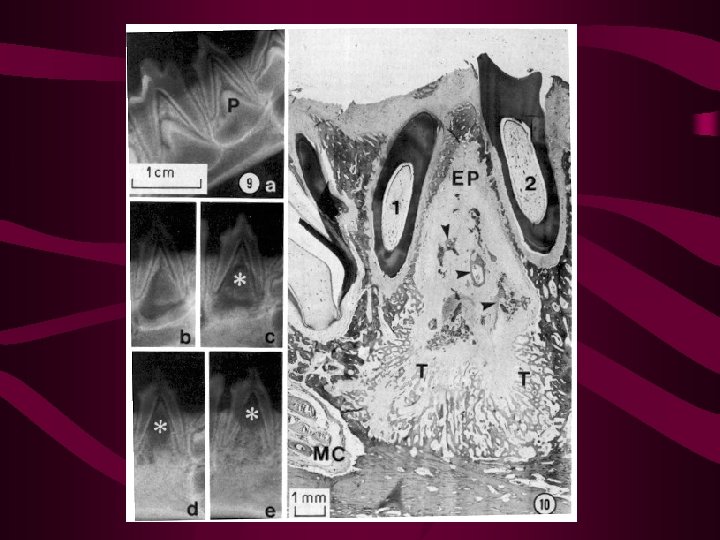

Gubernacular canal Gubernacular cord Eruptive Pathway

Histology of Sheding -Gubernacular Canal -Osteoclasts -Odontoclasts -Perio. Dontal Ligament